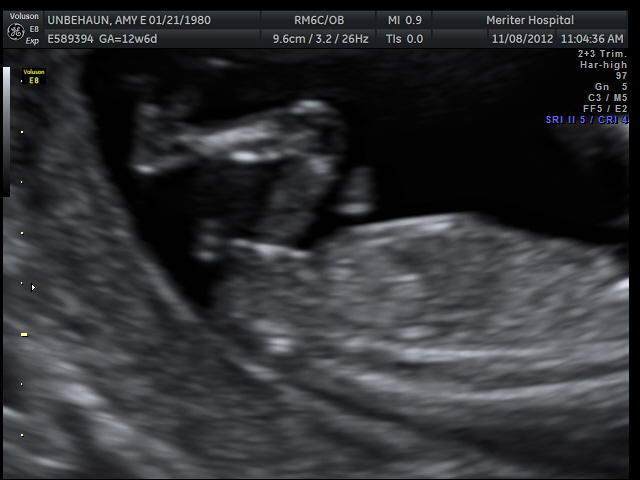

Nub guess please - 12w6d u/s